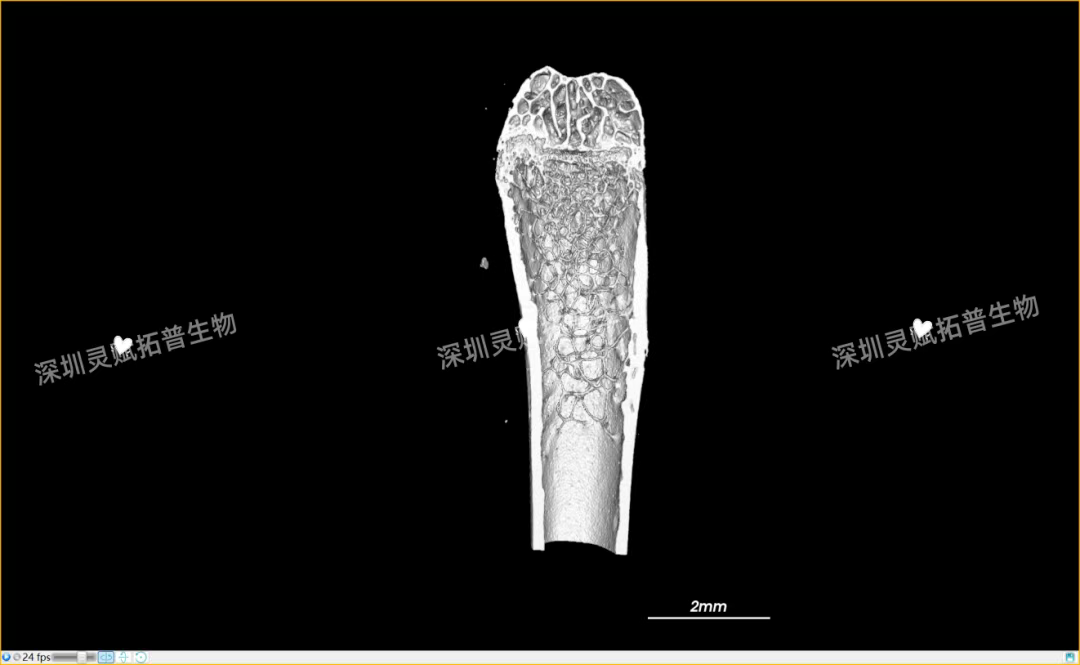

以小鼠股骨检测为代表,带大家直观感受J9国际站 J9 生物的服务实力:

本次实验对 E2 系列(E2-1、E2-2、E2-3)共3个小鼠股骨样本进行标准化扫描,取得了 0.5mm、2mm 等不同尺度的清晰成像,不仅直观呈现了股骨的宏观形态,更精准捕捉到骨小梁排列、皮质骨厚度等微观细节,为后续骨质疏松、骨修复等相关研究给予了可靠的量化数据支撑。

下附E2系列的典型案例:小鼠股骨扫描成像图